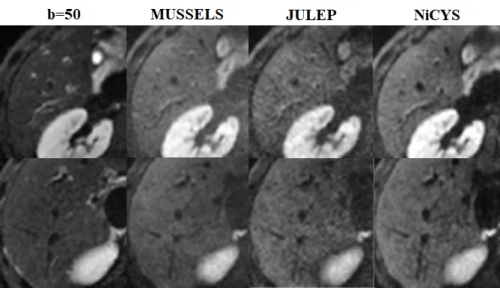

体部高清弥散成像

体部高清弥散成像作为MRI创新技术,对临床诊断意义重大。为了解决多激发高清弥散因运动带来的相位问题,东软医疗联合厦门大学,推出基于运动相位建模的系列高清扩散成像重建算法,配合多激发交错式平面回波序列采集的信号重建,可实现体部的高清扩散成像,助力病变精准分析。